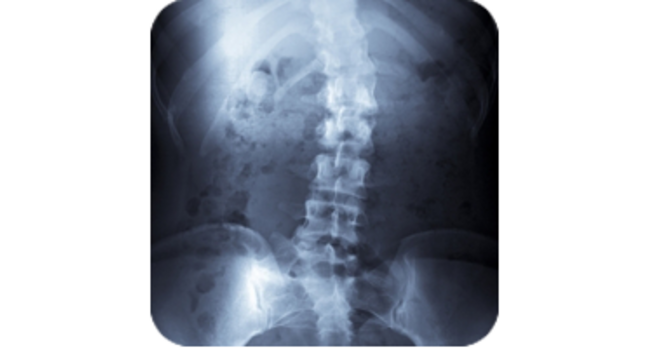

Here, you will find our collection of informative newsletters that cover a variety of important health and wellness topics. These complimentary newsletters are provided so that you may improve your understanding of chiropractic care and learn more about the fascinating abilities of our bodies!